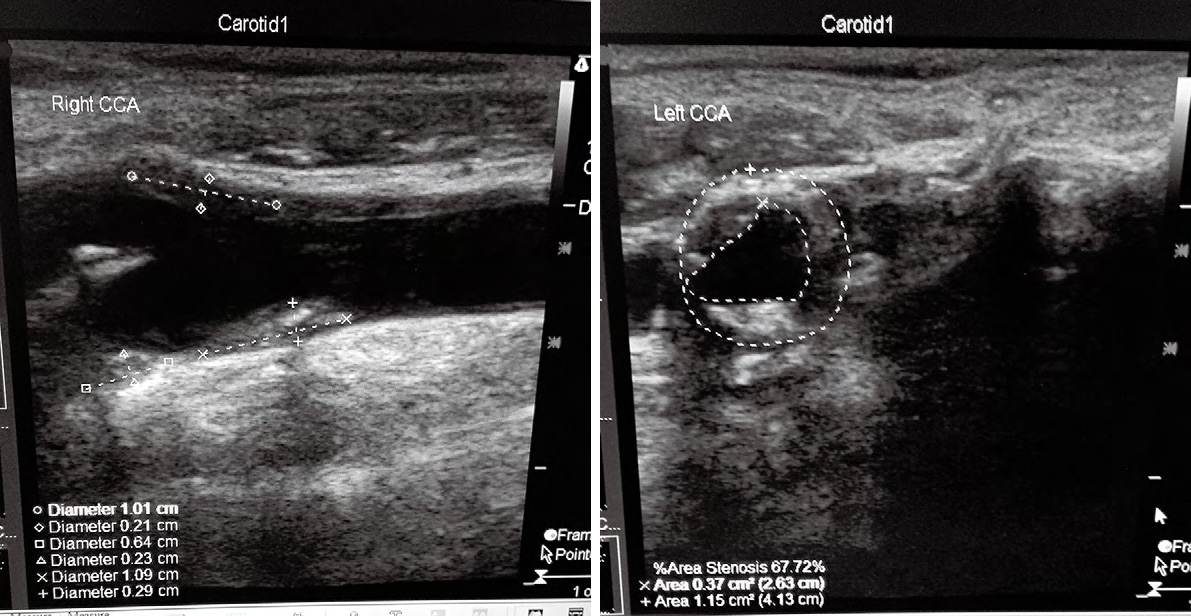

1、2114例患者中的典型病,老年男,主訴為頭昏伴雙手麻木不適數(shù),加重1周來我院神經(jīng)科門診就,TCD和頸動脈超聲聯(lián)合檢查進行早期篩查。檢查結果如下:

1TCD示:雙側(cè)頸內(nèi)動脈末-大腦中動脈流速顯著增快,伴頻譜紊亂,渦流形成, 考慮雙側(cè)頸內(nèi)動脈末-大腦中動脈狹窄;壓頸試驗后證實右側(cè)大腦前動脈、雙側(cè)大腦后動脈代償;腦血管彈性減退

2 頸動脈超聲提示:雙側(cè)頸動脈及椎動脈硬化;雙側(cè)頸部數(shù)個多發(fā)性動脈粥樣硬化斑塊形成;右側(cè)頸總動脈球部斑塊處管腔輕度狹窄;左側(cè)頸總動脈球部斑塊處管腔中度狹窄